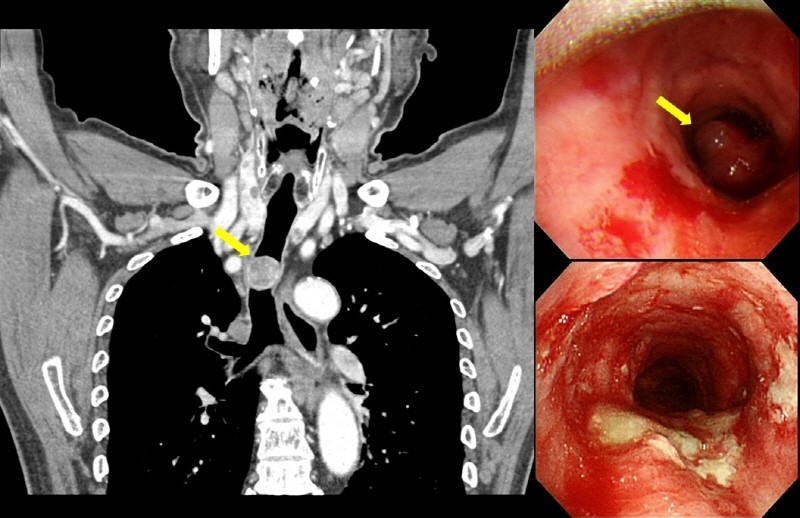

호흡기내과 지원준 교수는 환자 호흡곤란을 완화하고 진단을 위한 조직 채취를 위해 중재기관지내시경을 시행, 종양을 가능한 만큼만 제거한 후 스텐트를 삽입해 기도를 확보했다.

이때 제거된 종양 조직을 병리과 안보경 교수가 분석한 결과, 매우 드문 형태의 양성인 사구맥관근종으로 확인됐다.

사구맥관근종은 일반적으로 손가락 등에 흔히 생기는 사구종 중에서도 혈관이 발달해 있고 평활근 조직으로 구성됐다.

중심부 기도에 생기는 사구종은 흔치 않은데, 특히 기도 내 사구맥관근종은 전 세계적으로 3건만 증례 보고됐을 정도로 극히 드물다.

하지만 병리과 진단결과 종양 형태가 혈관을 많이 포함하고 있으며 단단하고 주변 조직과의 경계가 좋지 않아 심하게 기침하면 절제된 종양과 삽입된 스텐트 사이 자극으로 쉽게 출혈이 발생했다.

의료진은 기관지 내 출혈로 인한 혈전이 다시 중심부 기관지나 스텐트 내부를 막아 재발 가능성이 있다고 판단, 기관 내 잔존하는 종양을 모두 제거 후 심장혈관흉부외과 김용희 교수에게 수술을 의뢰했다.

김용희 교수팀은 환자가 폐렴으로 인한 전신 쇠약 상태이며 혈관종 특성상 출혈이 많을 것으로 예상했고, 종양 위치가 우측 무명 동맥 기시부에 위치해서 통상적인 접근이 매우 어렵다고 판단했다.